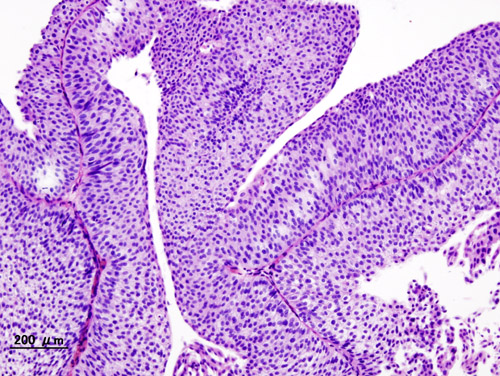

Urothelial carcinoma arises via two distinct pathways:

- Flat

- Papillary

Flat urothelial carcinoma is characterized by the invasion of a high-grade flat tumor and is associated with p53 early mutations.

Papillary urothelial carcinoma initially appears as a low-grade papillary tumor, advances to a high-grade papillary tumor, then invades, and is not linked to early p53 mutations.

A field defect is when a tumor recurs and is frequently multifocal in nature.